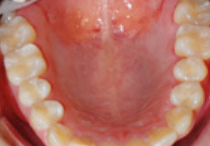

옆의 치아와

닿은 부위가

썩은 경우